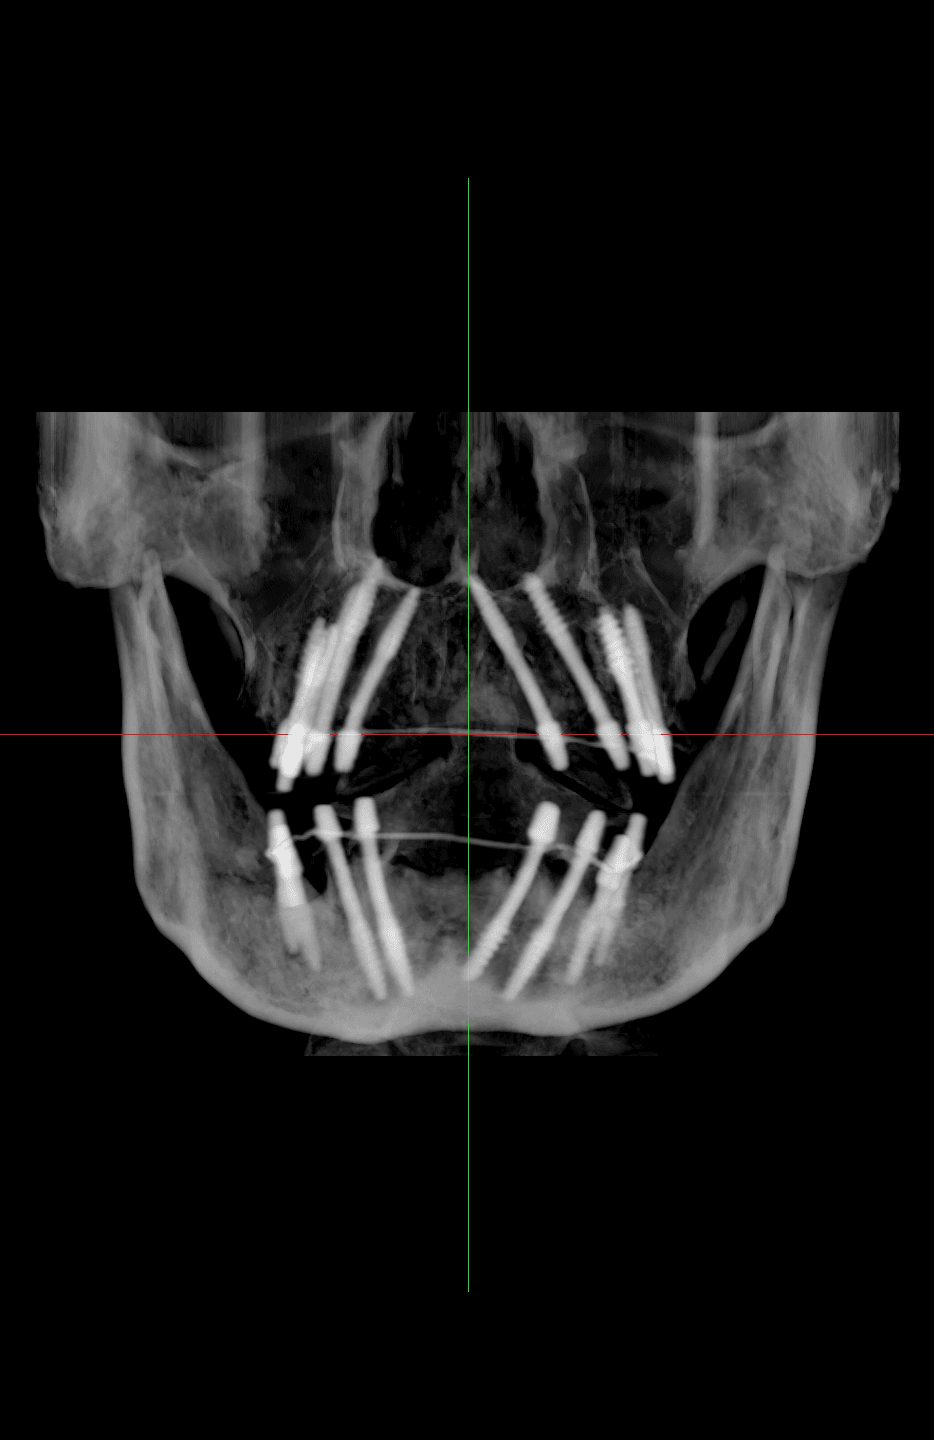

Analyzing force distribution and stress shielding in atrophied jaws using finite element analysis (FEA) based on our CBCT data.

Evaluating cortical bone stability and density changes post-loading over 12, 24, and 36 months.

Systematic pre-operative, intra-operative, and post-operative CBCT scans.